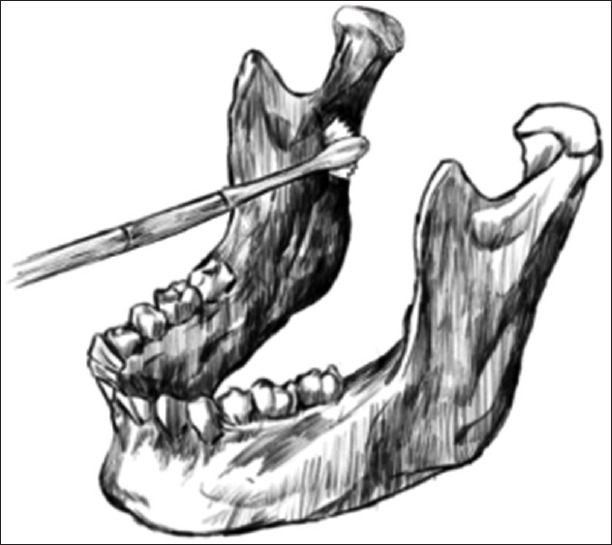

Outcome: The broken saw was pushed laterally from the medial aspect of the ramus using a periosteal elevator and retrieved from the lateral aspect of the mandible with curved haemostatic forceps without complications.